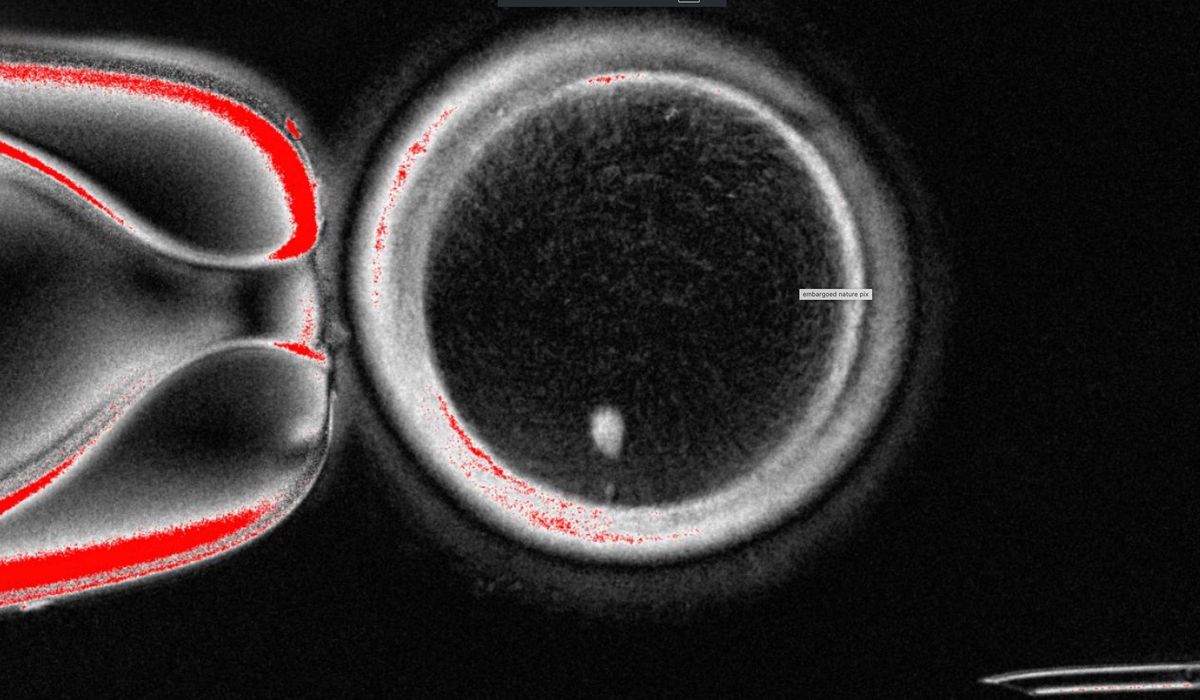

The OHSU team removed the nucleus from a human egg cell and replaced it with the nucleus from a human skin cell. But a skin cell contains two sets of chromosomes, and eggs and sperm are supposed to each contain only one set that combine during fertilization. The researchers therefore induced the egg-like cells to discard extra chromosomes, injected donated sperm and jump-started post-fertilization development.

About 9% lasted for six days in lab dishes, reaching the blastocyst stage of early embryo development, before the experiment was stopped.